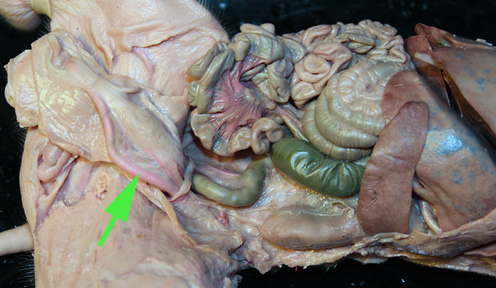

Areas of diffuse lymphatic tissue are found in the walls of the structures marked by the green arrows. They are called the///small intestine

The diffuse lymphatic tissue found in the structure marked by the green arrow is called peyer's PATCH

The green arrow is indicating the peyer's patch in this area of the small intestine. It is made up of a dense accumulation of what kind of cells?//lymphocytes